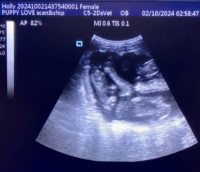

Mobile Ultrasound Pregnancy Scanning and Microchipping Services

Puppy Love scan and chip